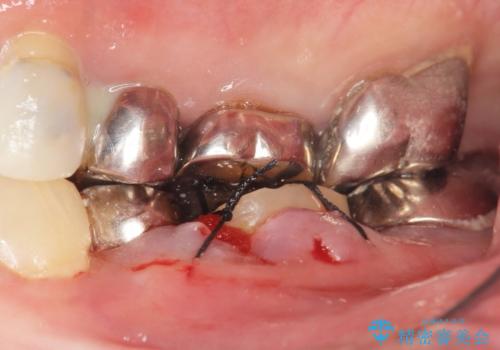

保存不可能な奥歯(左下6)を抜歯し、機能していない親知らず(左下8)の移植を行いました。

移植後、生着を待って根管治療及び補綴修復を行いました。